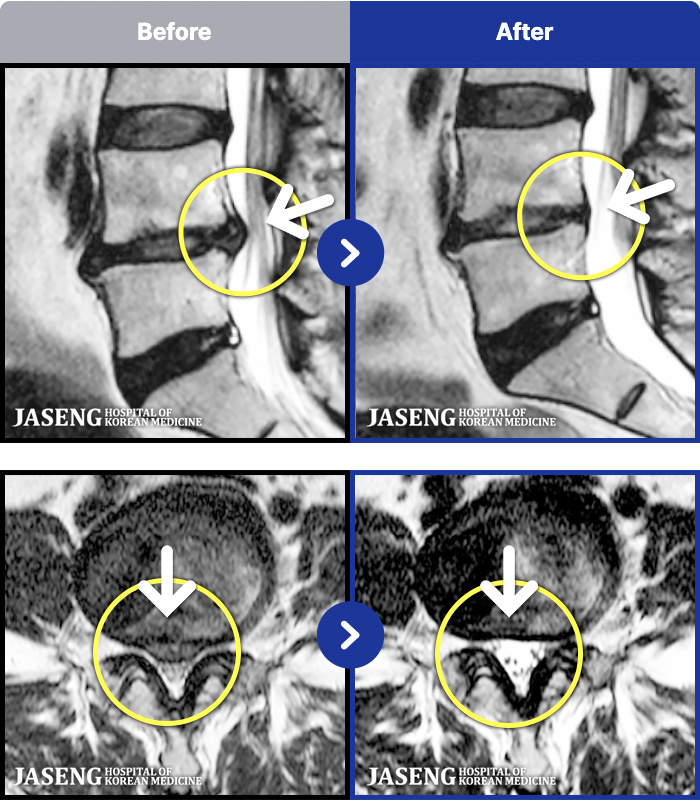

MRI ġ

MRI ũ ʸ Ȯϼ.